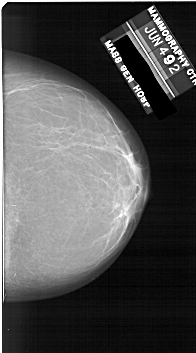

A_1860_1.LEFT_CC

LEFT_CC LINES 6061 PIXELS_PER_LINE 3451 BITS_PER_PIXEL 12 RESOLUTION 43.5 OVERLAY

FILE: A_1860_1.LEFT_CC.OVERLAY

TOTAL_ABNORMALITIES 1

ABNORMALITY 1

LESION_TYPE MASS SHAPE IRREGULAR MARGINS ILL_DEFINED

ASSESSMENT 4

SUBTLETY 3

PATHOLOGY BENIGN

TOTAL_OUTLINES 1

BOUNDARY